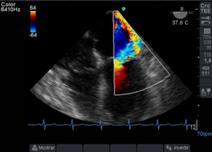

Luego con Doppler Color, analizamos la dirección del chorro regurgitante que es opuesta a la valva comprometida, el tamaño del jet regurgitante y su relación con el área de la aurícula izquierda (AI). Debemos tener en cuenta que el mapeo color del chorro regurgitante está influenciado por parámetros del ecógrafo: ganancia, PRF, límite de Nyquist, y por parámetros fisiológicos: presión arterial, volemia.

Otro factor que afecta el tamaño del chorro es la dirección de éste, los centrales en la aurícula aparecen más grandes con Doppler Color, que aquellos excéntricos que corren sobre la pared auricular, generando un efecto coanda (Figura 15), con un volumen regurgitante muy similar y que por su sola presencia le confiere severidad.

Figura 15 imagen de 4 cámaras medioesofágico con insuficiencia mitral severa, observada con Doppler color (escala 64) con efecto “coanda”, reflujo hacia la pared de AI.

Clasificamos la IM en leve si el área del jet es < 4cm2, o <20% del área de la AI; moderado de 4-8cm2 y severo mayor de 8cm2.